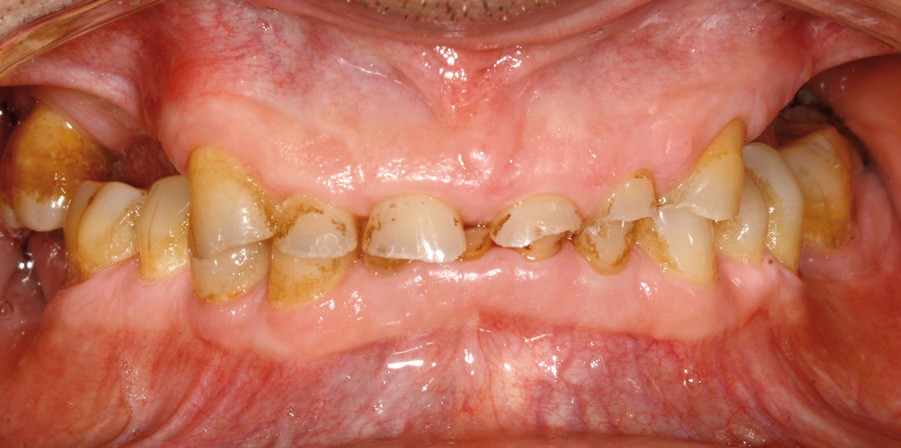

• L’examen intrabuccal montre de nombreux édentements non compensés (14, 15, 16, 24, 25, 26, 27, 47 et 36) ainsi que des pertes de substance très importantes, notamment dans le secteur antérieur.

Une attrition sévère, couplée à une occlusion sans calage postérieur, a engendré des difficultés pour s’alimenter.

• Le bilan esthétique nous indique plusieurs points disgracieux :

– dysharmonie des contours gingivaux (ligne des collets) avec une ligne du sourire basse [1] ;

– perte de substance extrême du bloc incisivo-canin maxillaire et des incisives mandibulaires ;

– visibilité très limitée des dents lors d’un sourire forcé ;

– égressions compensatoires.